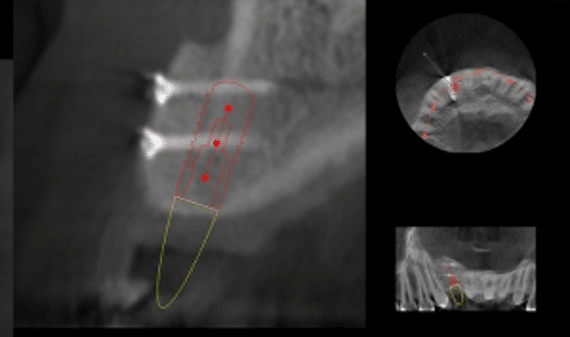

La mise en place de l’implant dentaire est réalisée après la cicatrisation de la greffe et un contrôle radiographique. Les vis d’ostéosynthèse sont déposées lors de la mise en place de l’implant dentaire.

Radiographie de contrôle d’une greffe osseuse d’apposition